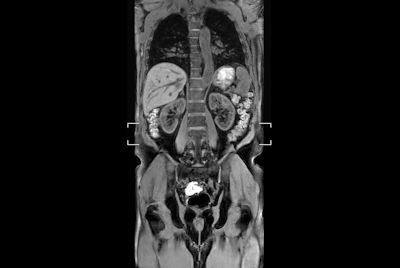

Total Torso with SmartShim